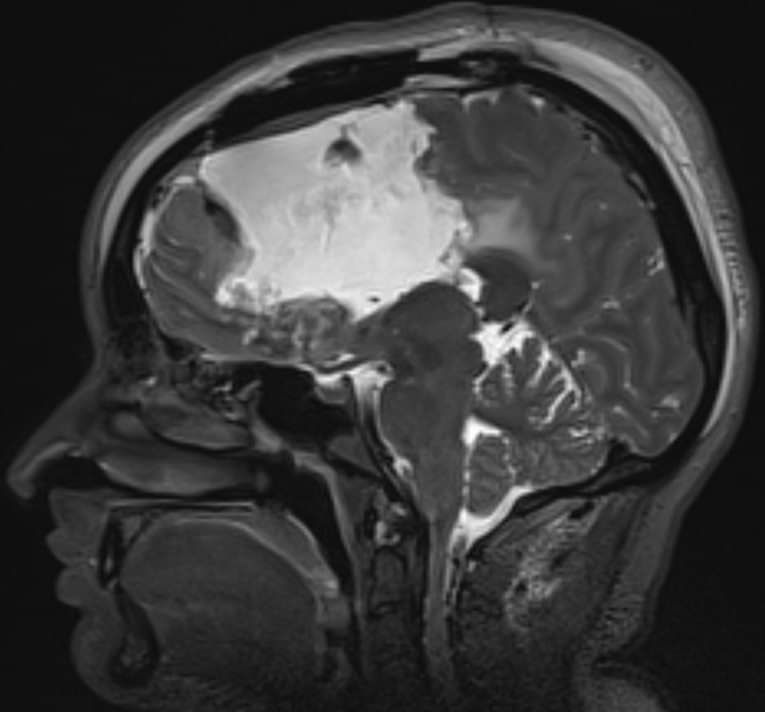

Чуть больше месяца назад в отделение поступила девушка 33 лет с жалобами на периодическую головную боль и однократный эпизод утраты сознания. При МРТ головного мозга выявлена большая опухоль обеих лобных долей с поражением мозолистого тела, размером 11,1х6,5х7,5см. (объем 283,3см3). Основной массив опухоли локализовался в левой лобной доле, подходя вплотную к зонам на коре, отвечающим за движения в правых конечностях и за произношение слов. В глубине опухоль находилась в непосредственной близости от речевых трактов и пирамидных трактов с двух сторон. Повреждение их могло привести к нарушениям речи или парализации пациентки. Мозолистое тело (структура, которая соединяет два полушария мозга между собой) было поражено опухолью на 75%. Разобщение полушарий (пересечение мозолистого тела) может привести к выраженным психическим нарушениям. В структуре опухоли проходили крупные сосуды, питающие до 30% полушарий. Все это делало предстоящую операцию действительно сложной. Так же напрягало еще то, что больную кроме умеренной головной боли ничего больше не беспокоило.

На послеоперационных МРТ видно, что опухоль удалена на 98,3%. Небольшой ее фрагмент в задних отделах пришлось оставить из-за прорастания ей двигательных зон.